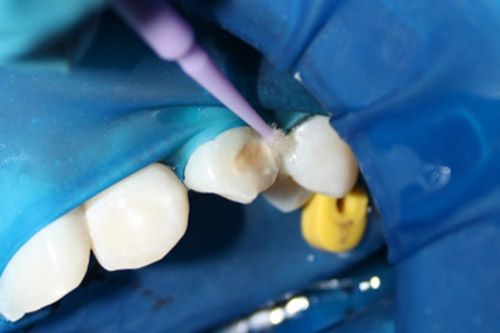

Se aplicó Icon Dry por 30 segundos.

Con la ayuda de un microbrush se aplicó el Icon infiltrant, frotando durante 3 minutos, posteriormente se polimerizó durante 40 segundos.

Se colocó por segunda vez Icon infiltrant en el contorno de la cavidad, pero solo por un minuto y se polimerizó por 40 segundos.